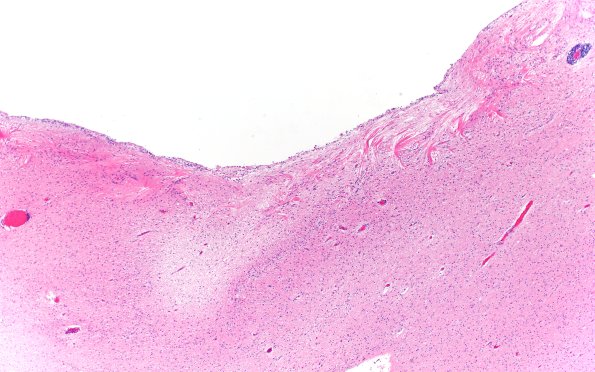

Washington University Experience | BASIC PROCESSES | Astrocytes & Astrocytosis | Astrocytosis | 11A4 Cerebral Palsy (Case 23) H&E 4X 2

A second site in the periventricular region of this patient showing prominent astrocytosis and wheat sheaving. Much of the ependymal lining of the ventricle has been lost. (H&E)